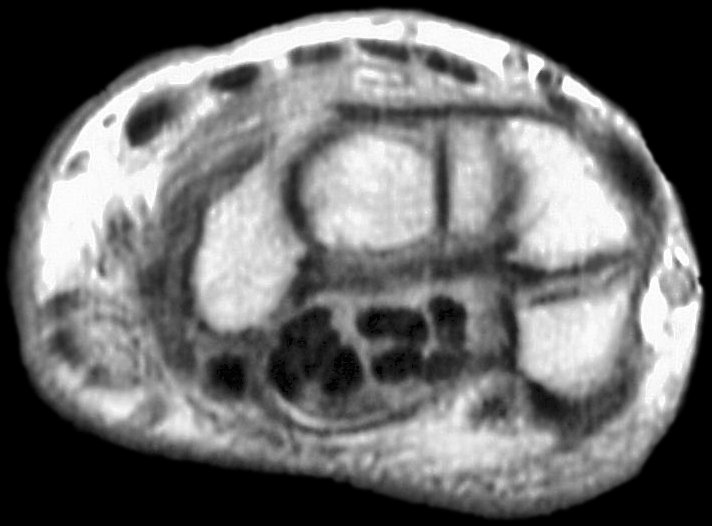

Sections through the carpal tunnel -  looking for a hook of hamate fracture or tendon discontinuity - were read as normal, although there may be a subtle signal irregularity through the hook of the hamate:

Is that a tendon rupture adjacent to the pisotriquetral joint?

The diagnosis was flexor tendon rupture, site uncertain. He was explored and found to have ruptured both flexors of the small finger within the carpal tunnel: